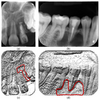

Marginal bone loss AND apical radiolucency affecting same tooth – diagnosis?

• Laesio endodontico-parodontica (endo-periodontal lesion).

• Treatment: Prognosis-dependent

X-ray shows widened PDL around entire root with marginal and apical involvement – diagnosis?

• Periodontitis totalis acuta (acute total periodontitis).

• Treatment: Extraction